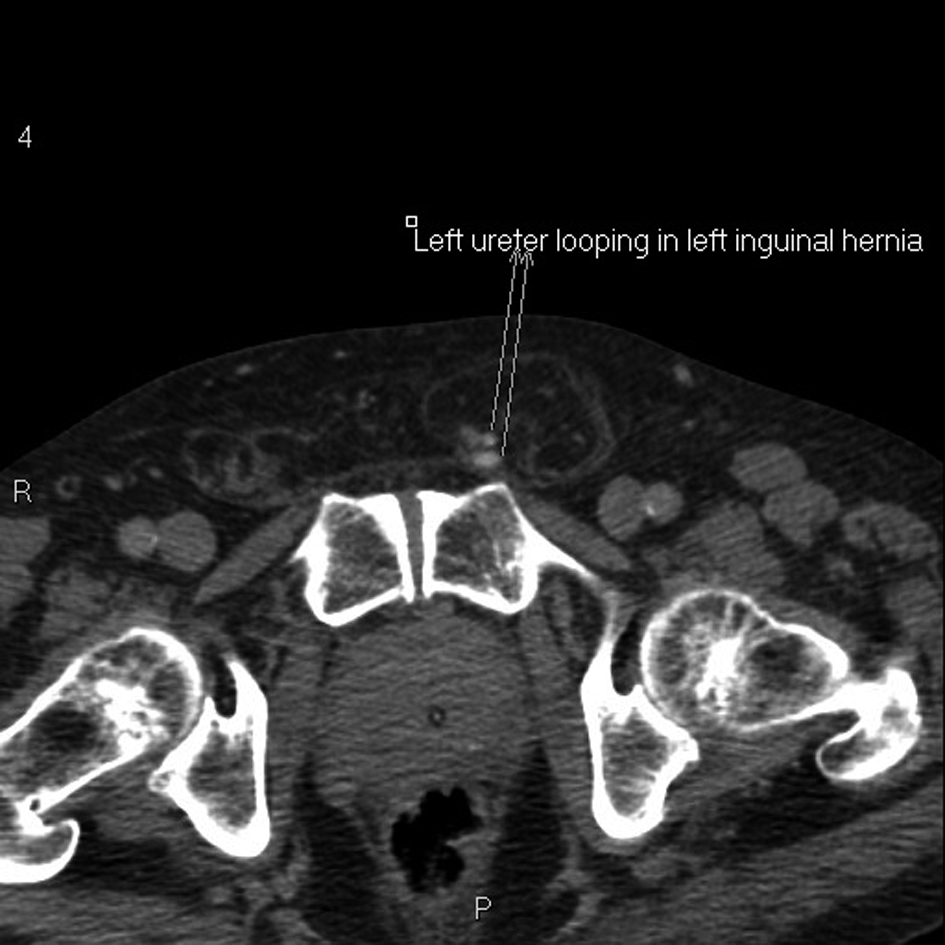

An 83-year old male with benign prostatic enlargement (BPE) presented with acute urinary retention with renal failure, constipation and weight loss. On examination, he had large bilateral asymptomatic inguinal herniae. Following catheterisation and medical renal failure management, a contrast-enhanced CT scan was performed to investigate his constitutional symptoms. An incidental finding was partial left ureteral duplication, and urography revealed that the distal part of one limb looped into the left inguinal hernia before inserting into the bladder (Fig. 1-4). The patient’s renal function normalised with catheterisation, which was definitive management of his BPE due to medical co-morbidities.

![]() Click for large image | Figure 3. Axial pelvic CT urogram demonstrating afferent and efferent part of the ureteric limb within the inguinal canal. |